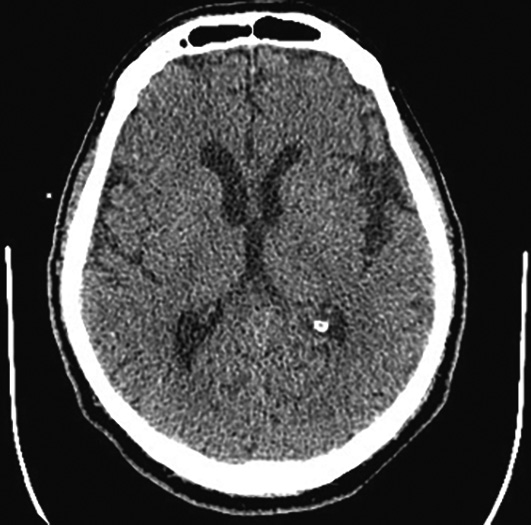

Учитывая характер бляшки по данным УЗДГ, отсутствие признаков геморрагического поражения, а также отсутствие ранних признаков ишемического поражения головного мозга по данным МСКТ, невозможность проведения тромболитической терапии (время от начала симптоматики более 4,5 ч), пациенту выполнена церебральная ангиография для определения показаний и принятия решения об эндоваскулярной тромбэкстракции. Выполнение перфузии головного мозга не проводилось, т.к. время от начала заболевания составило менее 6 ч [20]. На церебральной ангиографии выявлены стеноз правой ВСА в шейном сегменте (С1 сегмент) до 60% с признаками нестабильной бляшки (затёк контраста в полость ядра) и флотирующей интимы, стеноз правой ВСА в кавернозном сегменте (С4 сегмент) [21] до 90%. Левая ВСА, позвоночные артерии — без признаков стенозирования. Признаков артериовенозных мальформаций, аневризм головного мозга не выявлено. Тип Виллизиева круга был определён как разобщённый и классифицирован как тип Ac2Pc. Установлены отсутствие передней соединительной артерии, а также гипоплазия задних соединительных артерий [22] (рис. 2).

Церебральный кровоток в бассейне правой гемисферы — без признаков замедления, степень кровотока TICI3 (throm- bolysis in cerebral infarction) [23] (рис. 3).

Рис. 3. Церебральная ангиография пациента М. Выявлен стеноз правой ВСА в С1 сегменте до 60% с признаками флотирующей интимы и затёком контраста в ядро бляшки (чёрные стрелки). Стеноз до 90% ВСА в С4 сегменте (белые стрелки). / Fig. 3. Patient M.' cerebral angiography. Right ICA C1 stenosis to 60% with signs of floating intima and contrast agent leakage into the plaque core (black arrows) in. ICA C4 stenosis to 90% (white arrows).

Учитывая сохранение кровотока на уровне TICI3 по правым ВСА и средней мозговой артерии, а также повышенный риск геморрагической трансформации на фоне назначения антиагрегантной терапии и гепаринизации от экстренного стентирования решено отказаться в пользу первичной консервативной тактики. Через 24 ч после повторной МСКТ (рис. 4) рекомендовано начать двойную антиагрегантную терапию. Спустя 12 ч после госпитализации у пациента отмечен полный регресс симптоматики.